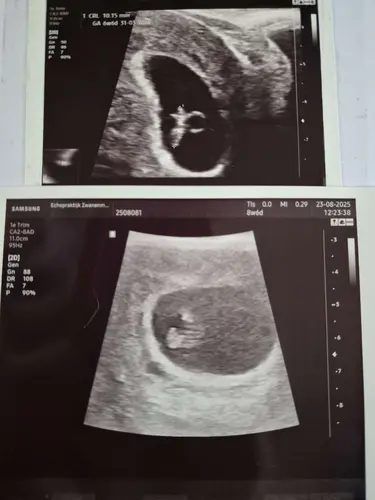

Nee, allebei uitwendig gek genoeg... Bij de eerste echo had ze ook niet zoveel moeite met scherp stellen. En nu was er onmogelijk iets duidelijk te krijgen 😞

kan best dat het 2 verschillende apparaten zijn geweest of dat dit apparaat gewoon niet goed werkte dat moment. of de echoscopist die het niet goed lukte.

ik denk niet teveel zorgen maken? in mijn ogen zie ik gewoon een foetus vormpje op die andere ogen.. ik weet niet of het aan mij ligt mja